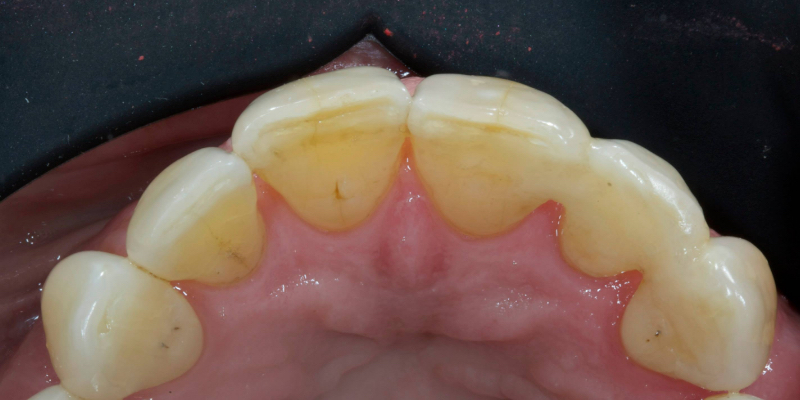

Take Arthur, a 76-year-old man who presented with a vertical root fracture of his upper left central incisor. His medical conditions precluded his request for an implant, so he agreed to the proposal for an adhesive bridge instead.

The tooth was extracted and for four months the pontic site was conditioned with a removable Essix-type of denture (Fig. 1).

An e.max (lithium disilicate), one-wing (adjacent central being the retainer) bridge was placed, which resulted in an acceptable outcome (Figs. 2-4) that was more timely and at a lower financial and biological cost to the patient than the implant Arthur initially thought he wanted.